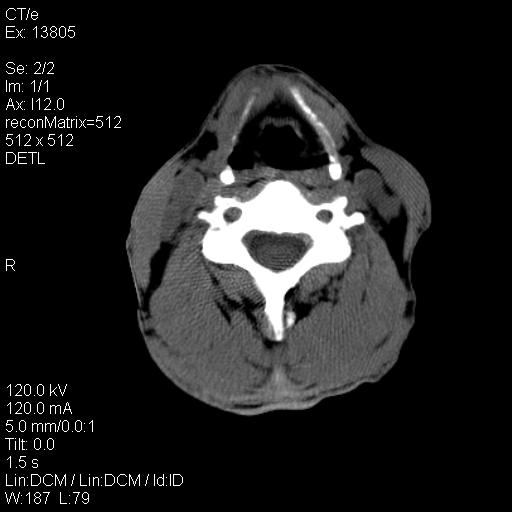

上腹部疼痛一月,呕吐10天,发现左侧颈部包快10天 胸部cr片未见明显异常。

左侧胸锁乳突肌下方、颈血管旁低密度肿块影,肿块密度尚均匀,边缘大部分清楚,邻近组织稍受压移位。考虑颈部神经鞘瘤可能性大。

颈部及腹膜后淋巴瘤可能性大